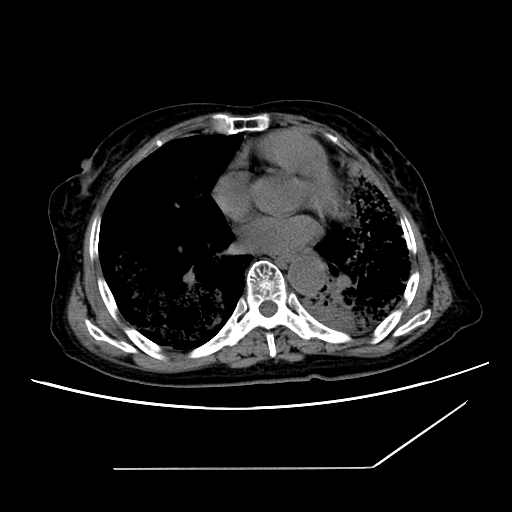

标题: CT25393:病人45岁,咳嗽,吐黄痰带血丝,发热,胸闷月余 [打印本页]

标题: CT25393:病人45岁,咳嗽,吐黄痰带血丝,发热,胸闷月余

1、左肺中央型肺癌并双肺弥漫性转移   2、双肺部感染    3、肺大泡     4、左侧胸腔积液

双侧肺弥漫性病变,可见“空泡征”及“蜂窝征”,考虑肺泡癌可能性大,左侧胸腔积液,考虑胸膜受累可能!

1)不排除肺泡癌可能。2)左侧胸腔积液。